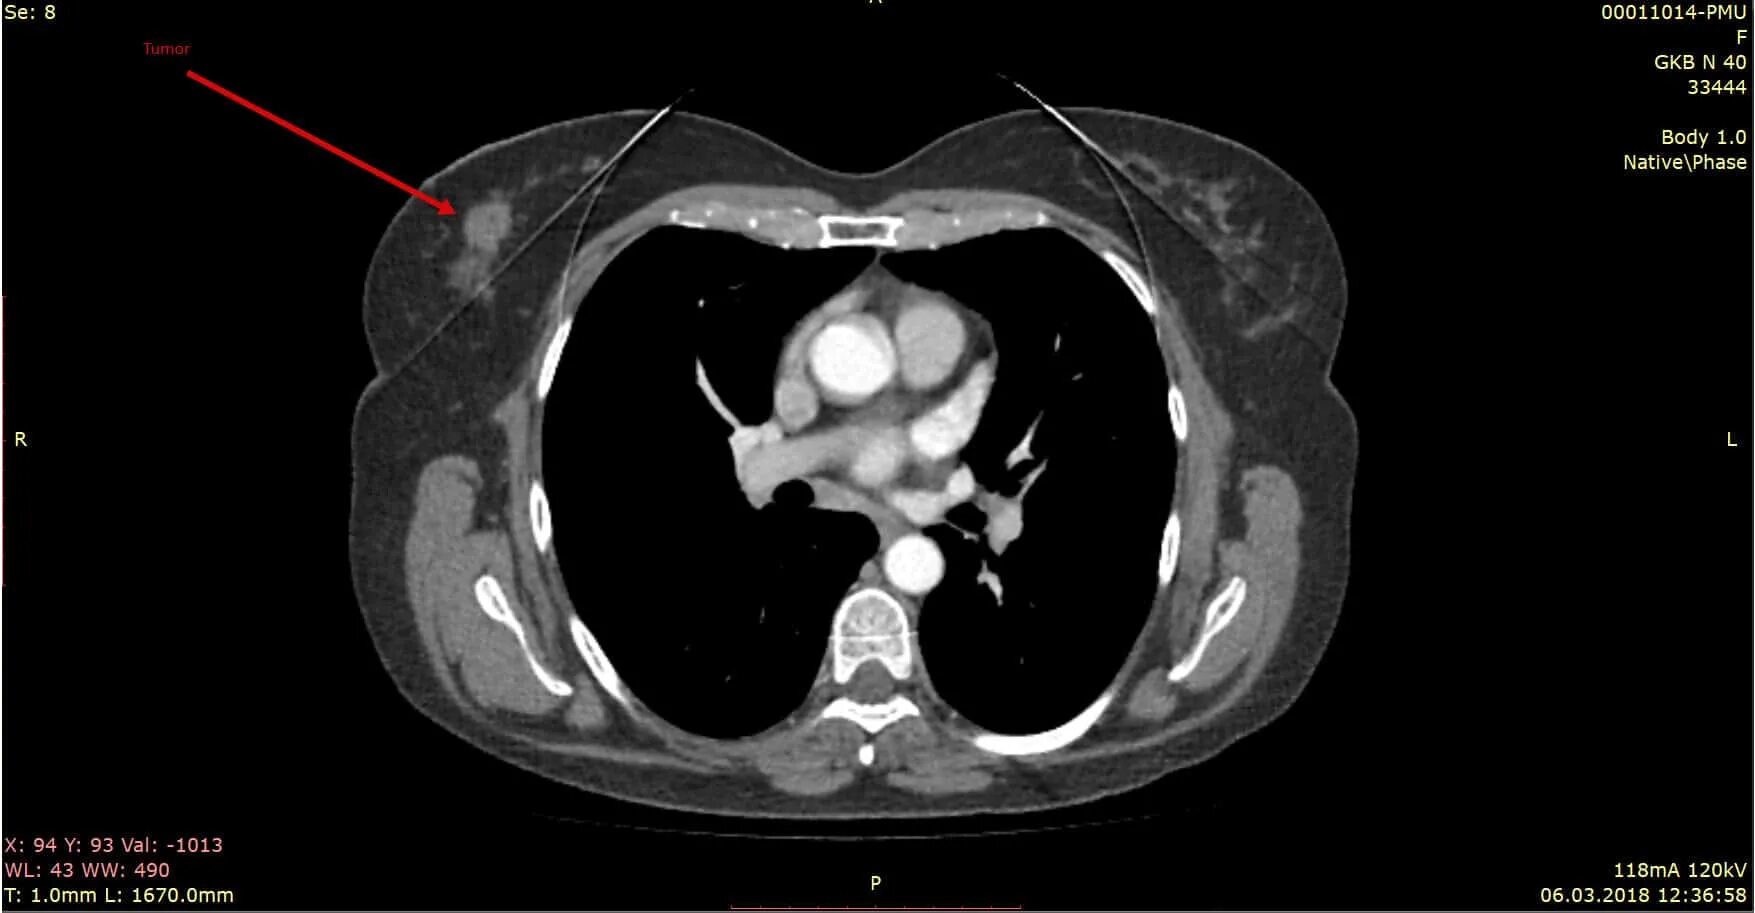

Делают ли кт молочных желез